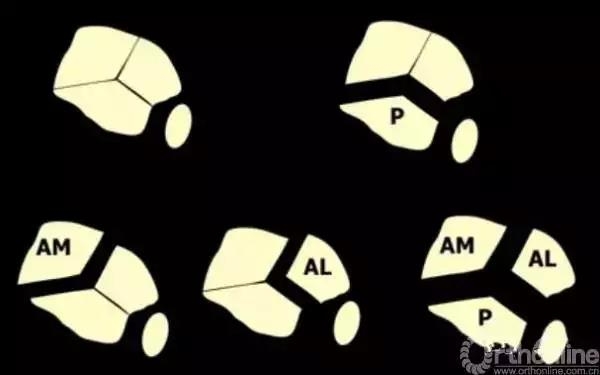

Pilon骨折手术入路选择原则一般取决于最适合进行关节面复位的入路。cole在2013年jot发表的文章描述了pilon骨折的骨折线图根据多例病例汇总到一起,颜色越深则越骨折线经过的可能性越大。

他将pilon骨折大致的骨块进行了分类,分别为后、前内、前外三个骨折块。Pilon骨折的入路一共有5个,前内、前正中、前外、后内、后外。